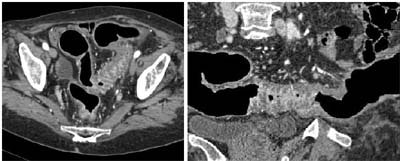

"This is the false-negative, a 9-mm Dukes A carcinoma in a length of sigmoid diverticulitis," she said. Unfortunately, the cancer remained undetectable using any type of image reconstruction. Even with prior knowledge of its presence, it could not be visualized in the typically low-attenuating diverticular wall of the stenosed segment.

![]() |

| Above, axial CT image (left) and curved reformat (right) shows severe stenosing diverticular disease. Within this area was a 9-mm Dukes A carcinoma, not detected as a distinct lesion on CT, but found on histology. Image courtesy of Dr. Alice Gillams. |